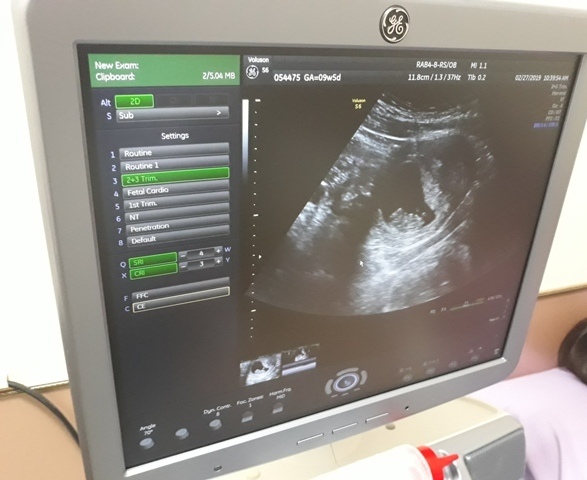

當小純進入診間看診時,我並沒有進去,因為小純說,有時男生不能進去,會被請出來。在外頭等待的我感到很緊張,不久之後,謢理人員請我進入診間,我嚇了一跳,想說發生什麼事了,進入之後,得知小純真的懷孕了,而且已懷了九星期又五天。看診的醫師說,驗孕棒第二條線淡淡的,沒想到胚胎照出來那麼大了,說Baby很健康。還說一閃一閃的是他的心跳,有頭、有手、有腳還有臍帶。小純後來說看了內心覺得很感動,才叫我一起進去看。

小純肚子裡的Baby超音波圖↓